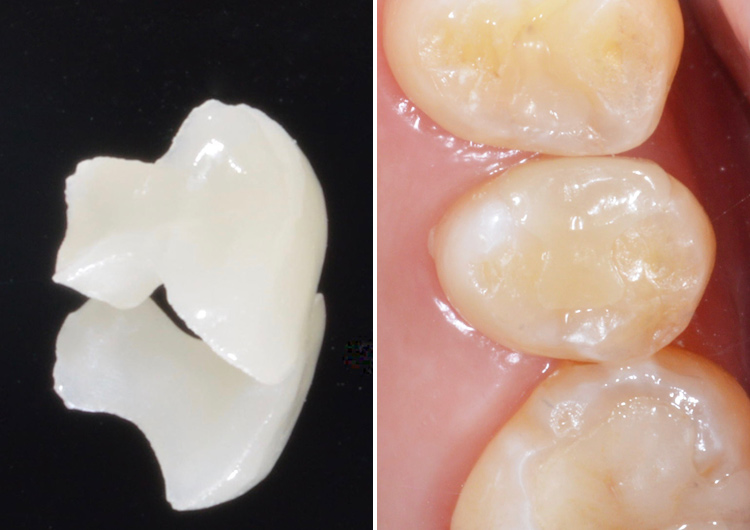

左上小臼歯の虫歯 セラミックインレー(e.max)による治療

治療途中

治療後

| 治療内容 | 検診で虫歯が見つかった。もともとプラスチックの詰め物で治療されていたが、その脇から虫歯になってしまっていた。 虫歯の再発をなるべく抑えたいとの希望があり、セラミックによる治療を選択。 1回目は虫歯の除去を行い仮詰め。2回目にデジタル印象(型取り)を行い、3回目にセラミックインレーを装着。 |